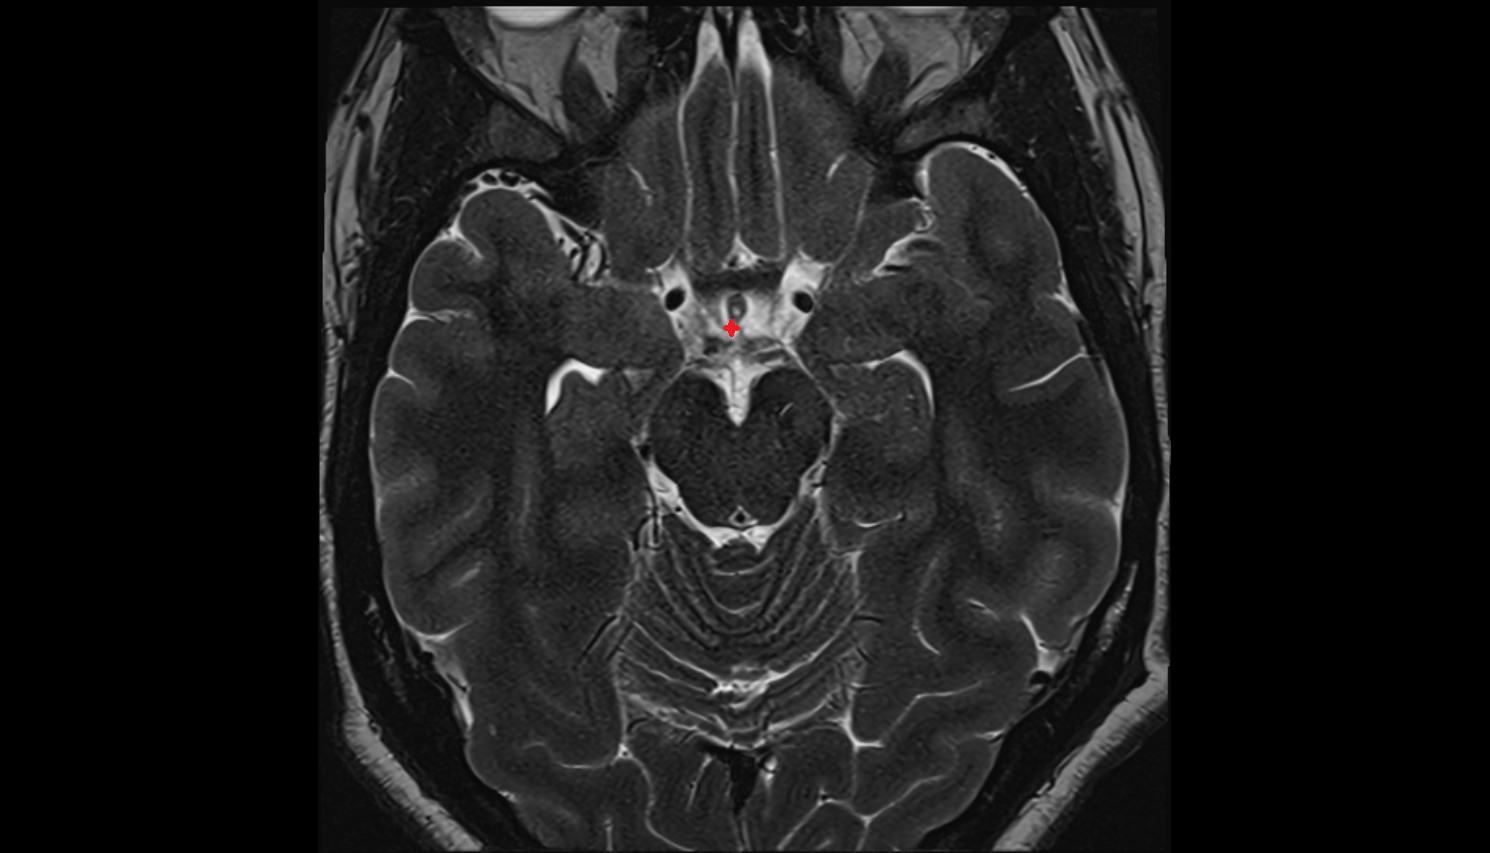

- Abducens nerve (Cranial nerve VI)

- Pons

- Median aperture of fourth ventricle (foramen of Magendie)

- Lateral aperture of fourth ventricle (foramen of Luschka)

- Cerebellopontine cistern